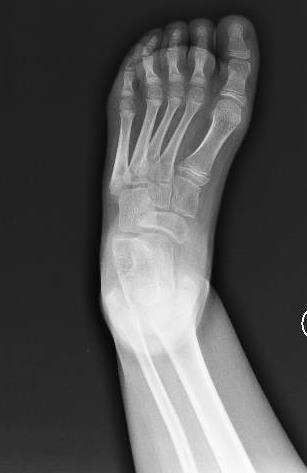

´Following orthopedic specialist visit, surgical correction of bilateral equinus foot was indicated

Fibrotomy-based Achilles tendon lengthening performed, achieving correction of equinus

• Bilateral selective segmental recruitment of the tibiotarsal joint

• Improved hindfoot control

• Transition from AFO to NH T2